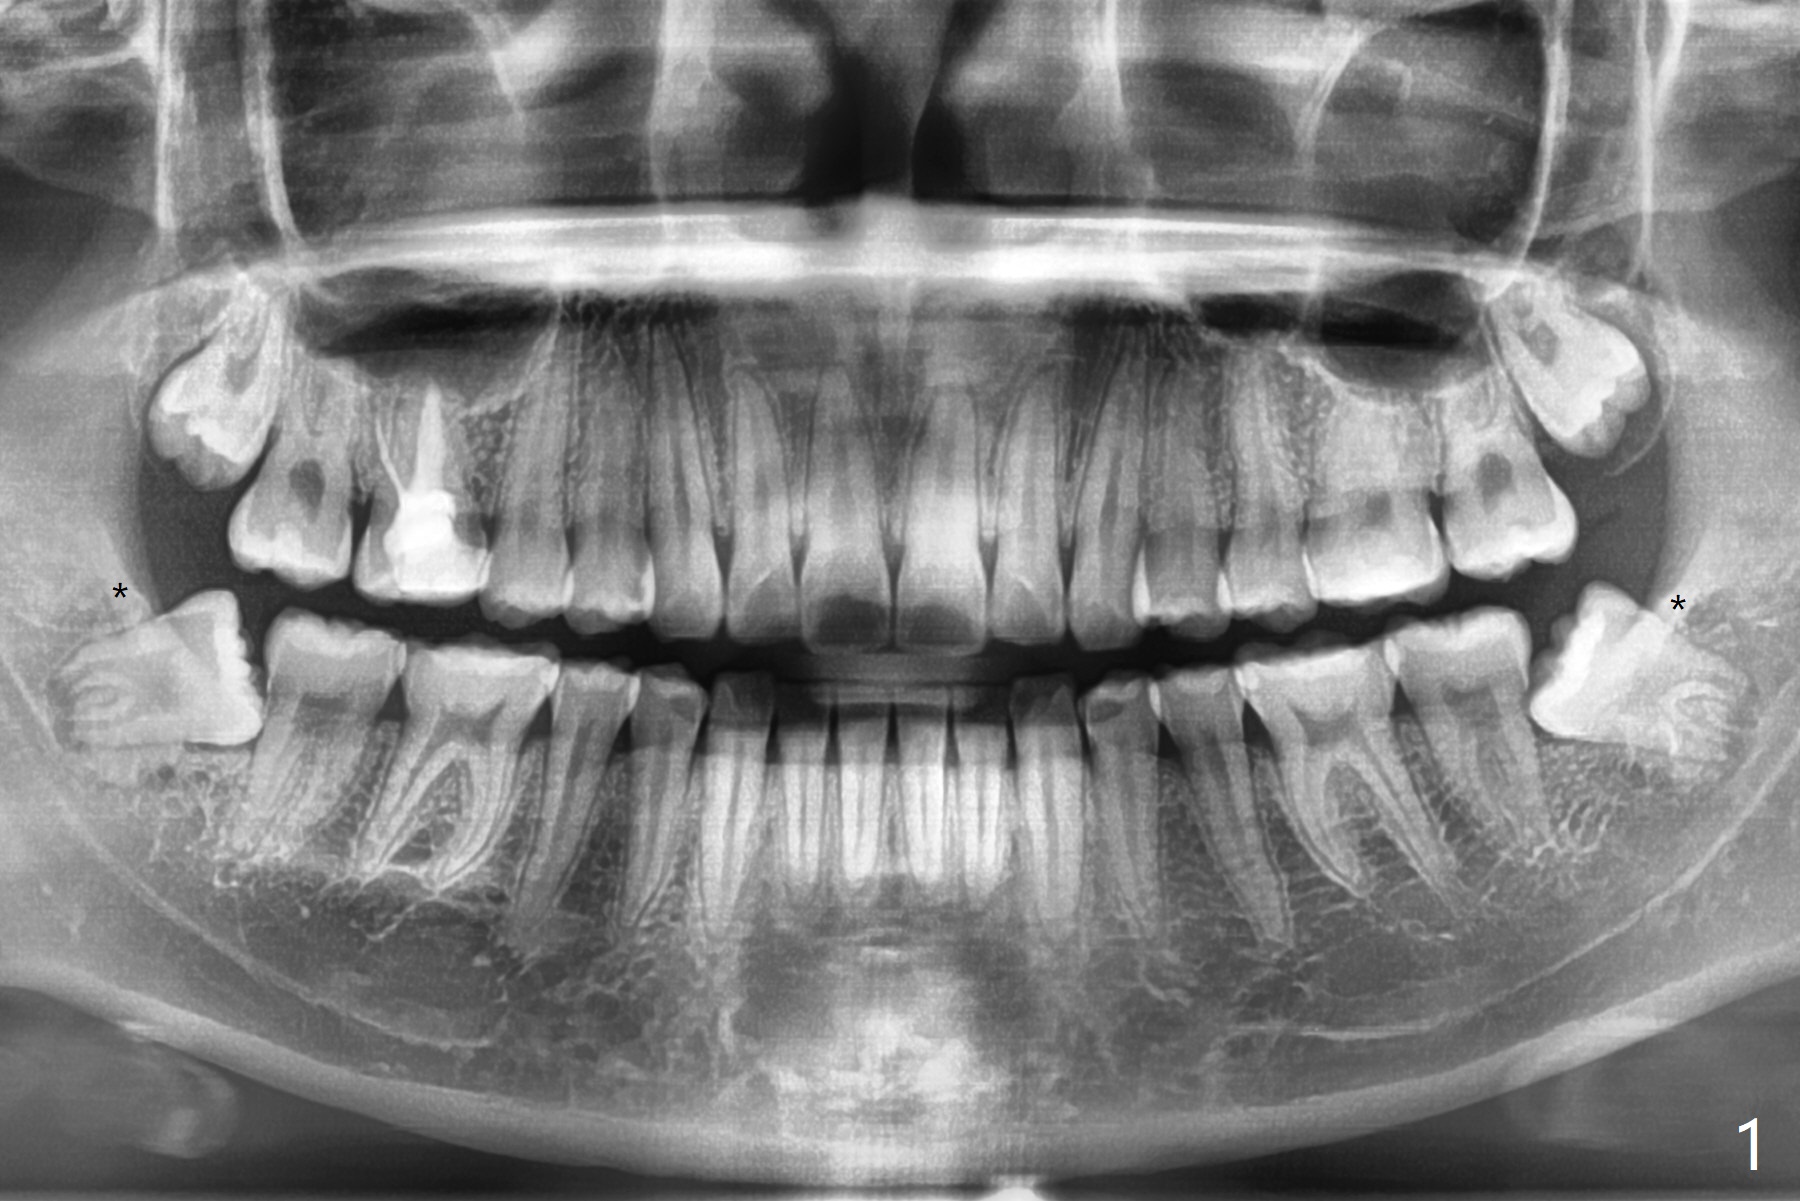

外斜嵴发育延申

20岁女由于右下智齿疼痛就诊,诊断后,要求先拔除两个下颌智齿。外斜嵴好像跨越牙槽窝远中(图一:*),拔除似乎没有缩短外斜嵴长度(图二:*),牙槽窝放置胶原塞。